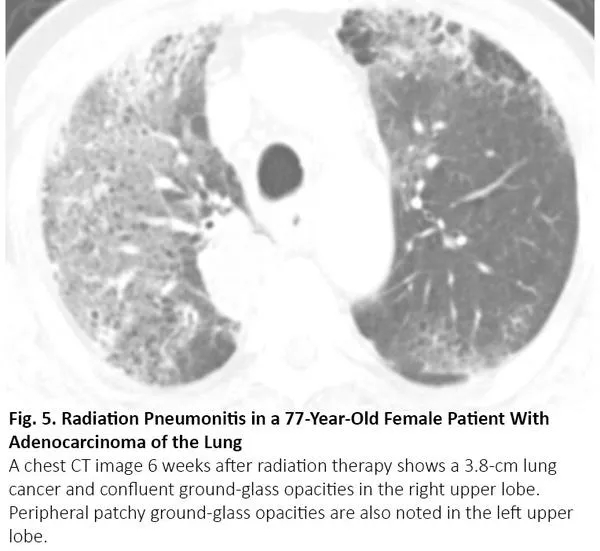

放疗结束后4~12周内可能发生放射性肺炎,有时更晚15。因为放射性肺炎通常发生在照射野,发生于局部,因此在大多数情况下,放射性肺炎与COVID-19肺炎的影像鉴别很简单。然而,当肺炎呈弥漫性分布时,可能无法将放射性肺炎与COVID-19肺炎区分(图5)。

图5. 一位77岁肺腺癌女性患者出现放射性肺炎

吸烟增加罹患肺癌和特发性肺纤维化(IPF)的风险,特发性肺纤维化患者罹患肺癌的风险会增加。当患者接受手术或放疗时,若特发性肺纤维化急性加重,CT可呈现双肺弥漫性或外周磨玻璃影,17与COVID-19肺炎相同(图7)。

图7. 一位72岁的小细胞肺癌女性患者出现特发性肺纤维化急性加重